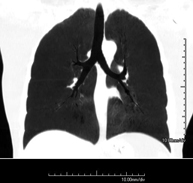

- Thorax

- Chest CT

Diagnostic test that provides high definition anatomical images of the chest (lungs, heart, mediastinum, great vessels, rib cage, etc.) using CT (Computed Tomography) equipment. These images are then examined on a workstation that allows bidimensional reconstructions in different planes of space and also 3D reconstructions (volumetric). Some studies require the use of an iodinated contrast agent to improve image definition.